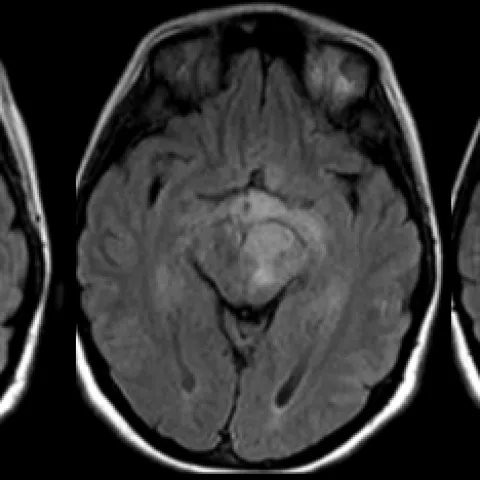

- Glioblastoma (GBM, WHO G IV): Commonest adult primary, aggressive, ring-enhancing, crosses midline. š "Butterfly glioma".

ā Glioblastoma (GBM) typically shows central necrosis, significant vasogenic edema, and peripheral enhancement, often crossing the corpus callosum ("butterfly glioma").

- Glioblastoma (GBM): Most common adult primary brain tumor, often crosses midline.